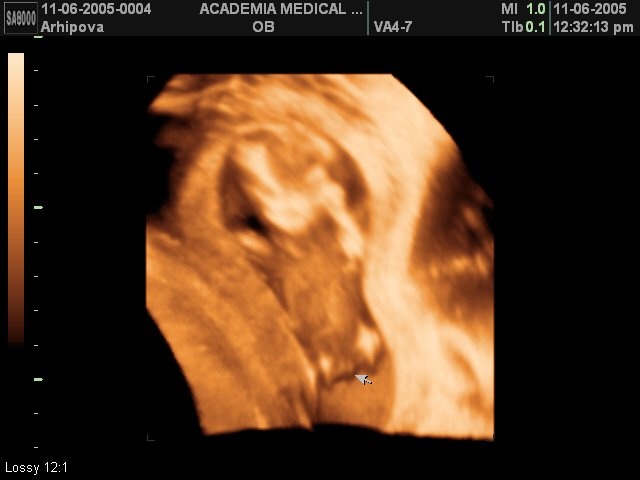

делали скрининг фотку в 3д формате делали сказали предположительно только,вот в 20 точно скажут

Простите за вопрос, а какое у вас УЗИ 3д или 4 д, просто очень хороший снимок, тоже такой хочу и где вы делали?

Честно не знаю.приехала на первый скрининг.и там вот так хорошо сфоткали.клиника находиться в домодедовском районе

Это город Домодедово.клиника женского здоровья.находиться прям возле дороги.в интернете забейте и высветиться.за скрининг первый платила 2370.просто за узи в 5 недель платила 1200.если что пишите:)

ок, спасибо большое, я много смотрела снимков с узи и могу сказать, что у Вас очень хороший, хочется и у себя иметь что-то такое, такая память))))